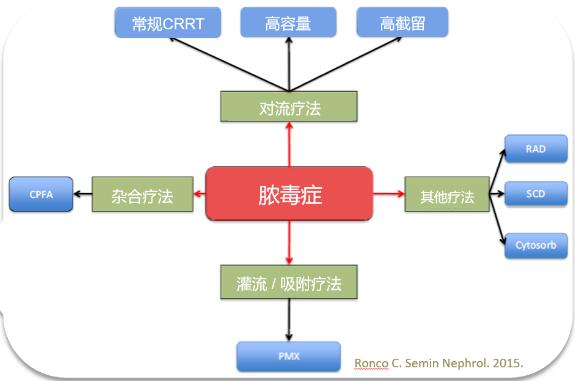

脓毒症相关急性肾损伤,我们有哪些体外血液净化技术可选择?

2023-11-13